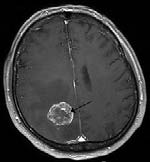

Figure 1: Brain tumour MRI: Magnetic resonance imaging (MRI) of the brain is a safe and painless test that uses a magnetic field and radio waves to produce detailed images of the brain and the brain stem. An MRI scanner consists of a large doughnut-shaped magnet that often has a tunnel in the center. Patients are placed on a table that slides into the tunnel. During the exam, radio waves manipulate the magnetic position of the atoms of the body, which are picked up by a powerful antenna and sent to a computer. The computer performs millions of calculations, resulting in clear, cross-sectional black and white images of the body. These images can be converted into three-dimensional (3-D) pictures of the scanned area. This helps pinpoint problems in the brain and the brain stem when the scan focuses on those areas [3].